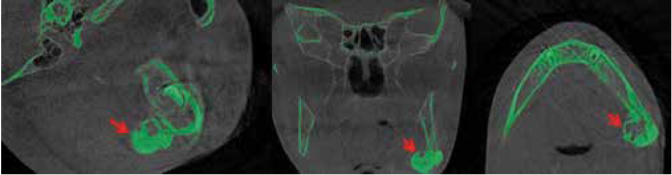

An 8-years-old boy reported to the Department of Oral and Maxillofacial Surgery, Ondokuz Mayis University with a chief complaint of hard swelling in the left posterior region of the mandible. The patient was physically healthy and any systemic condition was not detected during anamnesis. The swelling was not associated with any pain, discharge, fever, paresthesia, or difficulty in mastication. The patient did not recall or confirm any history of trauma or infection in that region. On clinical examination, a solitary, non-pulsatile and approximately 1.5 cm in diameter, bony mass was palpated at the left angle region of the mandible. The tumor found fixed to the underlying bone and the skin overlying the tumor was in a healthy appearance. The panoramic radiography and cone beam computed tomography (CBCT) scan showed a well circumscribed, radiopaque mushroom like image located on the left angle of the mandible (Figure 1, Figure 2). The 3D reconstruction of the computed tomography image revealed a pedunculated homogeneous bony mass attached to the left angle of the mandible (Figure 3). The lesion was completely excised using an extra oral approach under general anesthesia (Figure 4). The surgical specimen was submitted for histopathological examination. Histopathological examination revealed a sclerotic lamellar bone nodule with almost no intertrabecular space (Figure 5). These features confirmed the final histopathologic diagnosis to be peripheral osteoma. The post-operative course was uneventful with a satisfactory healing (Figure 6) . The patient is still under follow-up.

Usage of the most effective imaging modality pose a crucial role in the conservative management of the osteomas. Different imaging modalities like occlusal and panoramic radiographs, Waters view, computerized tomography (CT), magnetic resonance imaging (MRI), or CBCT can be used for the radiographic examination of POs 28. It is reported that POs in the craniofacial region are best visualized and localized by means of CT 29,30. In most of the cases in the literature the radiographic examination of the osteoma was performed with CT (14-16,31-33. However, because of it requires less radiation doses and provides higher quality of images than CT scan, we preferred CBCT in the radiographic examination of our case. Also, different from the majority of other published cases of osteoma in the mandibular angle, we used 3D modelling in our case to perform the treatment more precisely. As far as we aware, there was only one published case which use CBCT scan and 3D modelling together for the management of the angle osteoma (13).